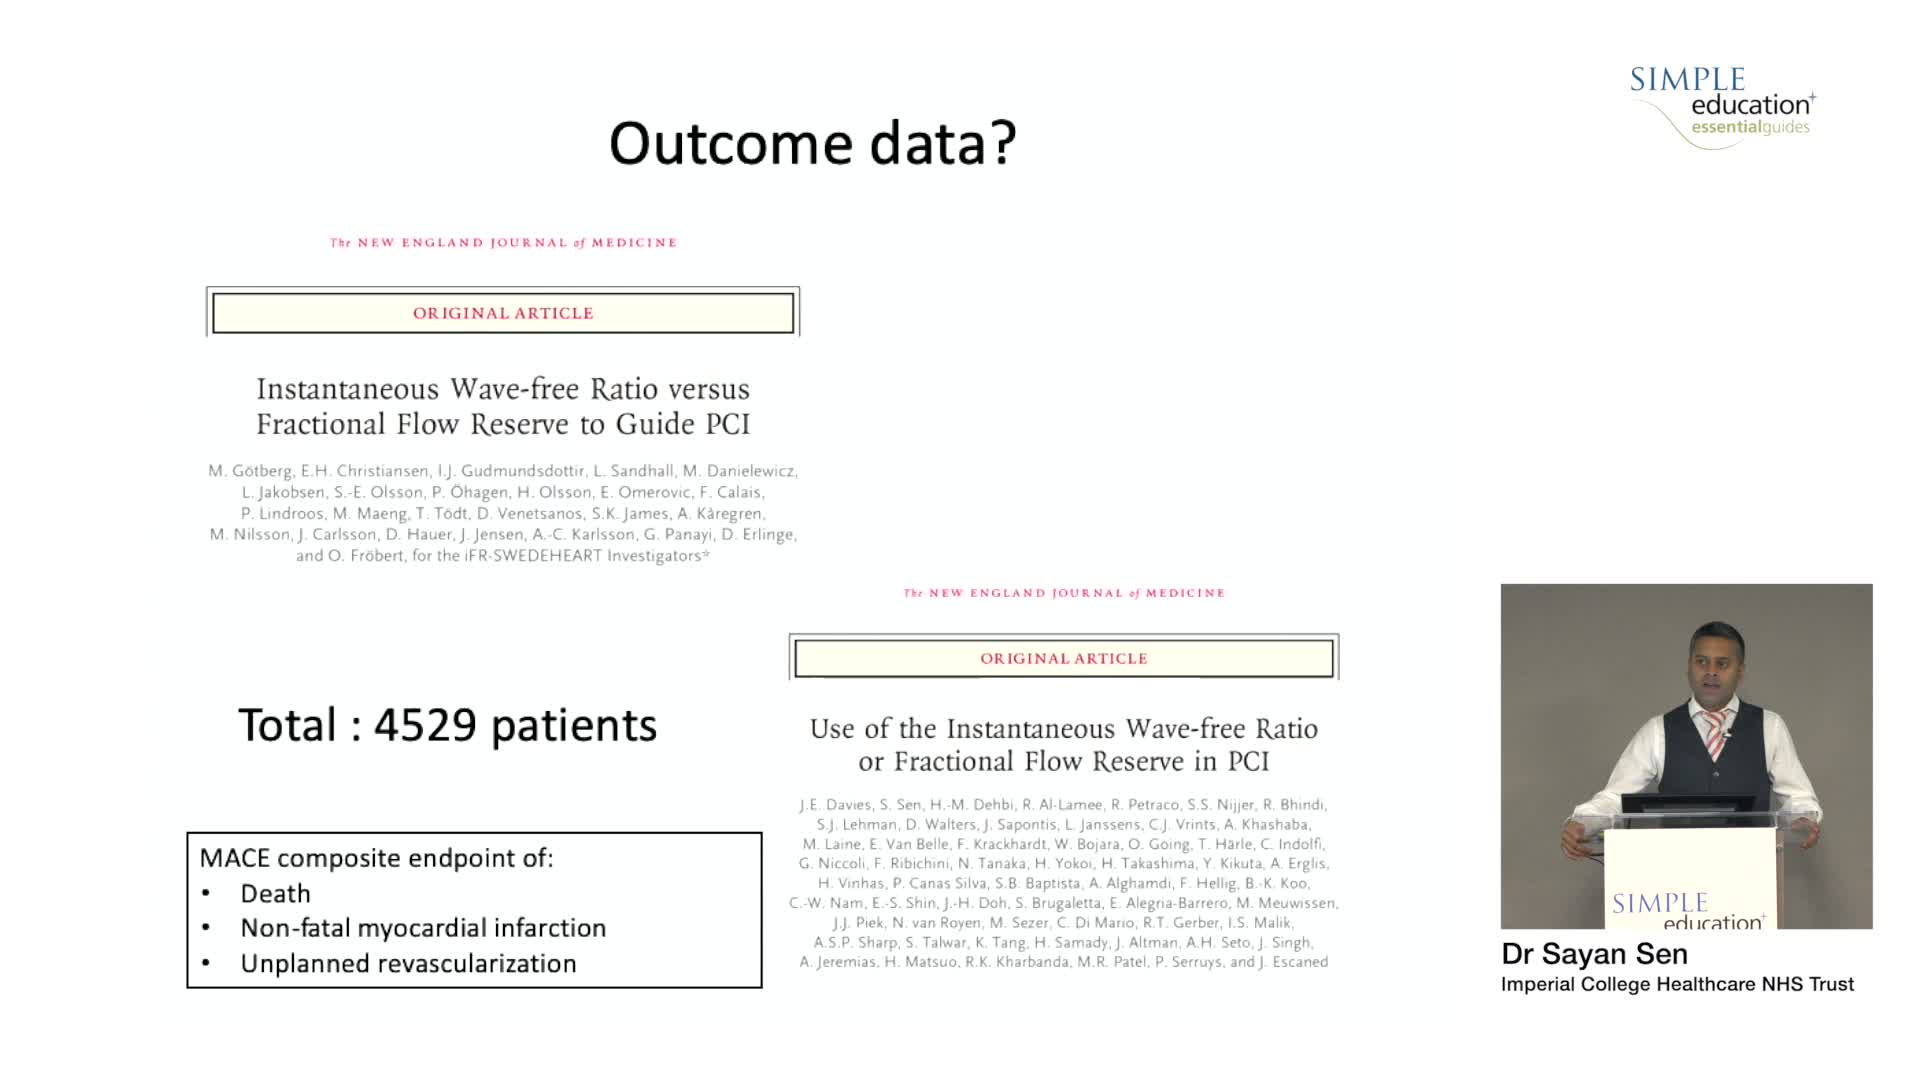

iFR or FFR in the LAD. What does the clinical outcome data tell us? - Dr Sayan Sen

DEFINE-GPS leading to full integration of coronary physiology to PCI decision-making

Coronary physiology gate keeper or guide to coronary PCI? Rationale and design of DEFINE-GPS